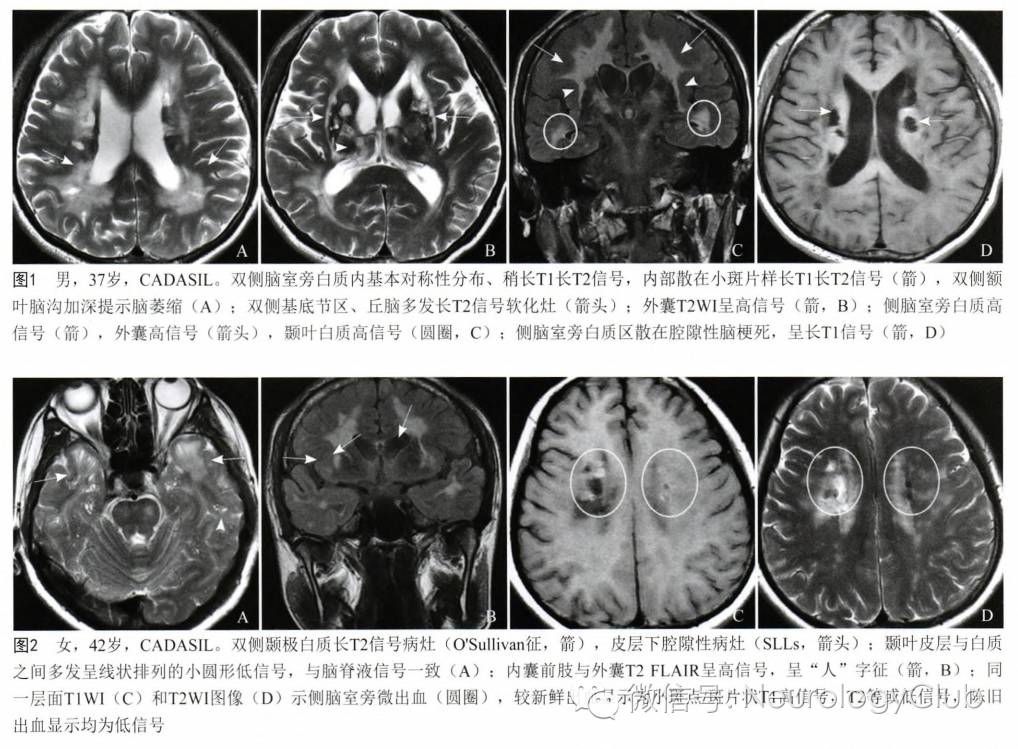

1脑白质病变

CADASIL患者在临床症状出现前即可有影像学上的改变。多对称分布,在MRI的T2像表现为大小不一的高信号,不累及弓状纤维。主要位于侧脑室周围和深部白质。以额叶白质最常受累,其次为颞叶和顶叶,而枕叶受损程度相对较轻。其中,外囊、颞极的对称性异常信号对诊断有高度提示作用。胼胝体亦可全层受累,引起胼胝体萎缩。皮层一般不受累。

疾病早期出现血管周围间隙加大,继而出现对称性孤立的单个结节状高信号区,此阶段容易与多发性硬化混淆。这些白质异常信号可以进一步扩大表现为外囊和颞极的高信号,对于年龄在20-30岁的亚临床患者,其颞极白质以及侧脑室周围出现帽状异常信号是其最早期的改变。随着病程进展双侧半球白质内大片长T2信号区相互融合,晚期小脑和脑干也受累及,约半数患者出现脑干长T2信号,其中脑桥(100%)比中脑(68%)和延髓(35%)更易受累,这一现象与年龄增长相关,出现双侧脑干病灶的CDADASIL患者可能预后不良。

颞极白质T2/FLAIR呈高信号是CADASIL的特征性表现,也称为O’Sullivan征,在 皮质下动脉硬化性脑病中无此现象,对本病的诊断敏感度为89%,特异度为86%。但O’Sullivan征对中国人CADASIL诊断并不是敏感指标。

外囊受累是CADASIL的另一特异征象,表现为T2/FLAIR高信号,诊断CADASIL的敏感度和特异度分别为93%和45%,并有助于CADASIL与其他小动脉疾病的鉴别诊断。本病也可累及基底节区内囊前肢额桥束,如外囊钩状纤维束和内囊前肢同时受累,在T2/FLAIR横轴位图像高信号呈“人”字征(Herringbone pattern)。

2腔隙性脑梗死

可广泛存在于大脑皮层下白质、基底节、丘脑、外囊、胼胝体和脑干等部位。腔隙性脑梗死在基底节的出现率高达100%,但出现在胼胝体和外囊等特殊部位的梗死灶更具有诊断价值。

3脑微出血

40岁以上的CADASIL患者通常会出现颅内微出血,直径多<5mm,微微出血部位由多到少依次为皮质和皮质下白质、脑干、丘脑、基底节和小脑。发生的比例在25%-69%之间,如此多的患者存在微出血,提醒广大临床医生针对此病应用抗凝治疗时应当非常小心。

(图3:T2WI可见CADASIL特征性的颞极高信号和外囊受累)

(图4:MRI上可见颞极、脑室旁和深部白质病变)

(图5:A:T1WI可见脑室旁低信号病灶;B-C:FLAIR可见脑室旁高信号病灶,外囊受累,基底节区可见腔隙性梗死)

(图7:T1WI可见脑干,丘脑和豆状核等处多发腔隙性梗死;B:FLAIR上可见深部小梗死灶伴累及前颞叶和外囊的弥漫融合的白质高信号;C:T2*可见丘脑和脑干多发小的低信号病灶,为微出血)

(图8:A-B:FLAIR上可见皮质-皮质下交界处多发低信号病灶[箭],为与血管周围间隙扩张有关的腔隙。这些病灶为CADASIL较为特异的影像学表现,见于约67%的患者,常伴有前颞叶融合的白质高信号)

(图9:A:颞极高信号病变;B:皮质下、外囊高信号病变;C-D:两例患者均有胼胝体受累[箭头])